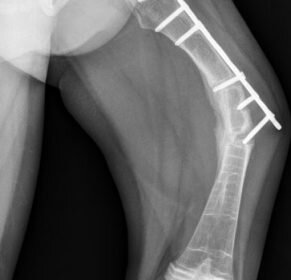

Многие дети с несовершенным остеогенезом, имеющие деформации конечностей, нуждаются в хирургическом лечении – выполнении корригирующих остеотомий с фиксацией металлическими конструкциями, которые предохраняют кость от повторных переломов. До недавнего времени для этого были доступны металлоконструкции, используемые в других областях травматологии и ортопедии. Они имеют постоянную длину и не удлиняются вместе с ростом кости. Это приводило к переломам выше и ниже металлоконструкции, что требовало многочисленных повторных операций

Этот вид лечения относится к высокотехнологичной медицинской помощи и доступен для граждан РФ.

На снимке: телескопический интрамедуллярный стрежень